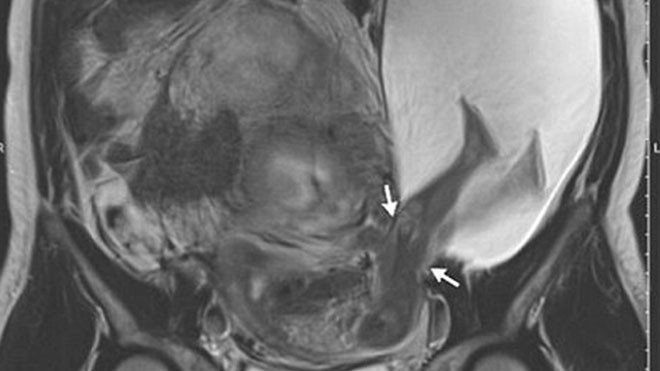

Hình chụp siêu âm cho thấy em bé đã đạp rách tử cung khi vẫn nằm trong bụng mẹ.

Trường hợp mang thai kỳ lạ này đã được bác sĩ Pierre Emmanuel Bouet, thuộc Bệnh viện Đại học Angers phát hiện ra sau khi nhìn thấy hình siêu âm của một sản phụ 33 tuổi. Theo bác sĩ, đây là 1 trong 26 ca mang thai cực hiếm hoi trong lịch sử y học thế giới.

Vết rách có chiều dài 2,5cm. Một phần túi nước ối cũng theo đó mà lòi ra ngoài. Trước tình trạng này, bác sĩ đã cảnh báo khả năng sinh non cũng như thoát vị tử cung, nhau cài răng lược, thậm chí phải cắt bỏ tử cung ở mẹ.